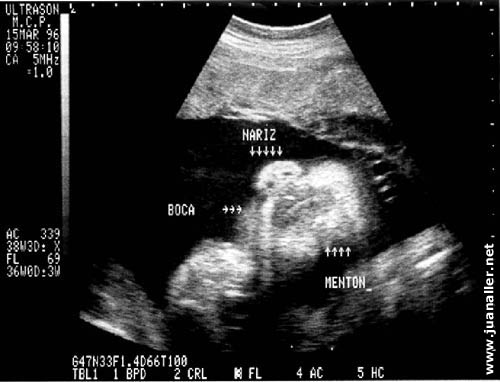

Estructuras de la cara | |

Durante este periodo se puede hacer lo siguiente:

- Determinar la edad, el crecimiento, posición y en alguna oportunidad el sexo del bebé